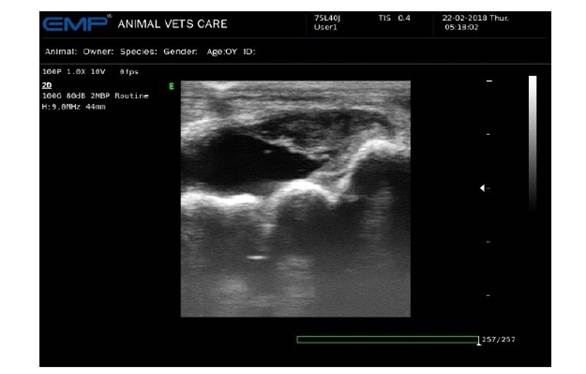

Figura 1 Imagen ecográfica de equino hembra de 4 años con historial de trauma en la región del tarso del miembro posterior derecho. Se observa distensión de la membrana sinovial con aumento del líquido (sinovitis). Obsérvese la sinovia de un aspecto hipoecogénico, heterogénea, con bandas de fibrina, indicando hemorragia intraarticular

Se realizan pruebas dinámicas con el fin de evaluar los posibles sitios de afección presentes en el miembro posterior de la paciente. El desplazamiento se clasifica como claudicación de apoyo con un grado 5/5; así mismo, son evidentes los movimientos compensatorios debido al dolor, apoyando en pinza mientras está en estación. Se realizan bloqueos perineurales para evaluar la sensibilidad del miembro y permitir analgesia para realizar una artrocentesis. Luego del bloqueo tibial y peroneo, el grado de claudicación disminuye a 3/5 y hay apoyo del aspecto solar del casco en estación. Se decide hacer una ecografía articular inicial para evaluar los tejidos blandos y el líquido articular, además de realizar la técnica de artrocentesis ecoguiada (Figura 1).

El ultrasonido articular se realiza con un ecógrafo Emperor Medical G30 con una sonda lineal a una frecuencia de 9 MHz. En el abordaje lateral de la articulación tarsocrural se observa distensión de la membrana sinovial, con aumento del volumen del líquido sinovial y cambios significativos en su ecogenicidad (hipoecogénico, de ecotextura heterogénea), y con presencia de material vegetativo relacionado a bandas de fibrina, las cuales podrían indicar hemorragia intraarticular o hemartrosis.